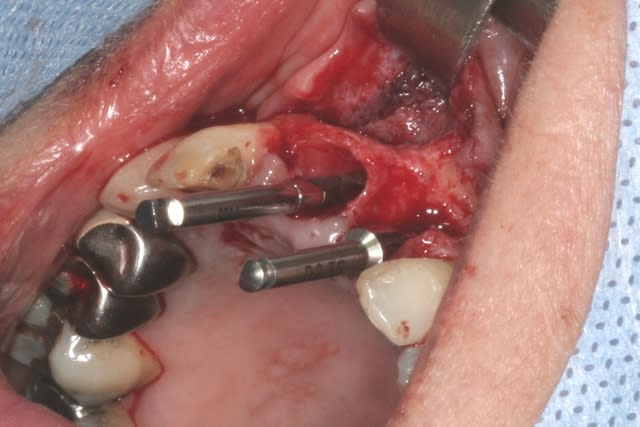

tien, ce matin, extraction de 24/25, curetage méticuleux, forage, comblement du gap, pose des 2 implants qui se sont bloqués à 50Ncm au CA sur les 3 ou 4 mm apicaux, pose des vis de cicat, sutures...35min....tranquille...

un autre cas EII MCI sur 11/21...mais en photos (j'ai aussi la vidéo, faut que je la passe sur youtube)

Voilà ce que l'on arrive à faire mais ce fut limite!